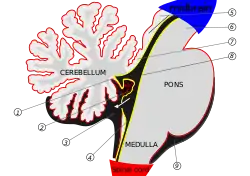

| T2-weighted sagittal MRI of Dandy–Walker variant (DWV) with dysplasia of the pons and cerebellar vermis in an 8-year old | |

Dandy–Walker malformation (DWM), also known as Dandy–Walker syndrome (DWS), is a rare congenital brain malformation in which the part joining the two hemispheres of the cerebellum (the cerebellar vermis) does not fully form, and the fourth ventricle and space behind the cerebellum (the posterior fossa) are enlarged with cerebrospinal fluid. Most of those affected develop hydrocephalus within the first year of life,[6] which can present as increasing head size, vomiting, excessive sleepiness, irritability, downward deviation of the eyes and seizures.[4] Other, less common symptoms are generally associated with comorbid genetic conditions and can include congenital heart defects, eye abnormalities, intellectual disability, congenital tumours, other brain defects such as agenesis of the corpus callosum, skeletal abnormalities, an occipital encephalocele or underdeveloped genitalia or kidneys.[5] It is sometimes discovered in adolescents or adults due to mental health problems.[5][6]

Pathophysiology

The cerebellum begins forming at the fifth week of embryonic development. It differentiates at the top of the metencephalon, while the pons (in the brainstem) differentiates at the bottom, separated by the fourth ventricle. The cerebellar hemispheres form from the rhombic lips on the forward surface of the fourth ventricle, which expand and roll over to fuse in the midline to form the cerebellar vermis by the 15th week. If this process does not complete, the cerebellar vermis will not form fully. This long period of development of the cerebellar vermis makes it particularly vulnerable to disruptions.[6]

In DWM, the fourth ventricle opens up into and is continuous with almost the entire posterior fossa subarachnoid space.[6]

Diagnosis

Dandy–Walker malformation is diagnosed based on the characteristic neuroimaging findings. It can be diagnosed prenatally on ultrasound as early as 14 weeks of gestation, although it is usually diagnosed postnatally by MRI. It is diagnosed within the first year of life 41% of the time, normally due to increasing signs of hydrocephalus,[18] but 28% of the time it is discovered in adolescence or adulthood due to mental health problems, such as psychosis or mood disorder.[5][6]

Criteria and classification

The precise diagnostic criteria and classification systems of DWM are not agreed upon, and significant dispute exists as to which terms or criteria should be used.[5][6][12] The core criteria of DWM are hypoplasia of the cerebellar vermis and an enlarged fourth ventricle and posterior fossa (the space behind the cerebellum), though the specific degree of hypoplasia or cystic enlargement for diagnosis of DWM is not agreed upon.[7] Additionally, there are several similar conditions which have at various times been grouped with DWM on a continuum by some authors and separated as distinct by others, further complicating diagnosis.[6][8]

Methods